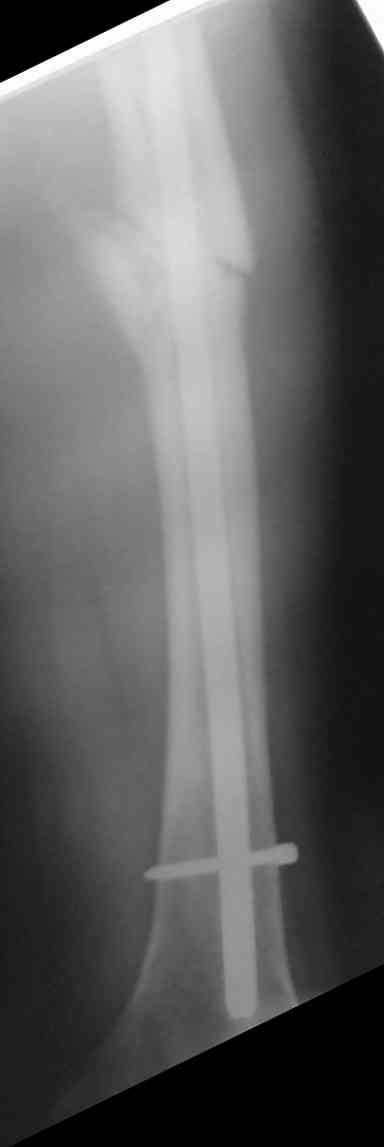

Мужчина 38 лет, получил травму ДТП 26.07.05, был оперирован 12.08.05(снимки 1 и 2), денамизация - февраль 2006. ( 3 и 4 снимки) на сегодняшний день (снимок 5)

беспокоит боли в тбс, и хромота.

клинически ходит самостоятельно с клюшкой прихрамывая. отмечается наружная ротация ниж. конечности. укорочение на 3,5 см.

сгибание и разгибание в тбс в полном объеме, ограничение ротации и отведения. объем движения в к\с полный.